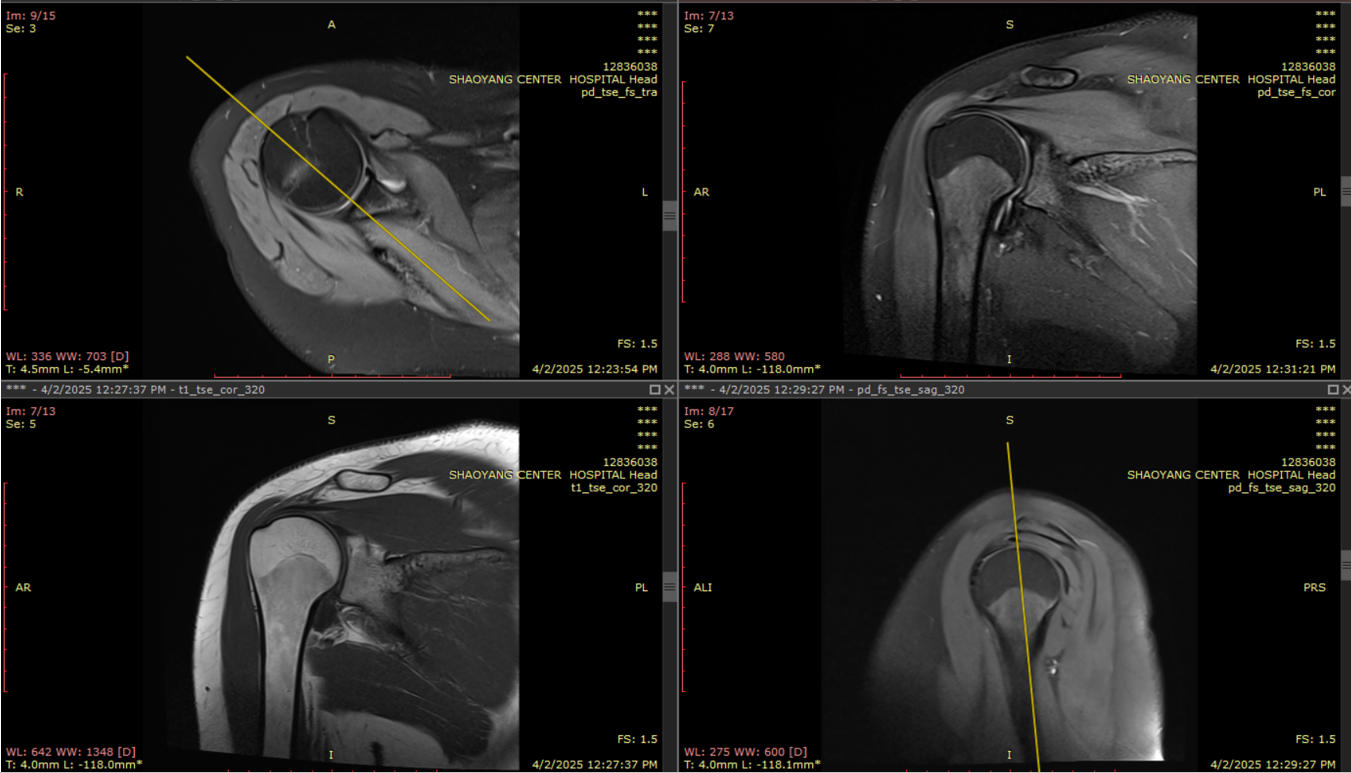

(3)关节线圈(膝关节、肩关节、腕关节等)

● 用途:韧带损伤、软骨磨损、关节炎、运动损伤等。

● 特点:小巧灵活,紧贴关节部位,提高图像细节。